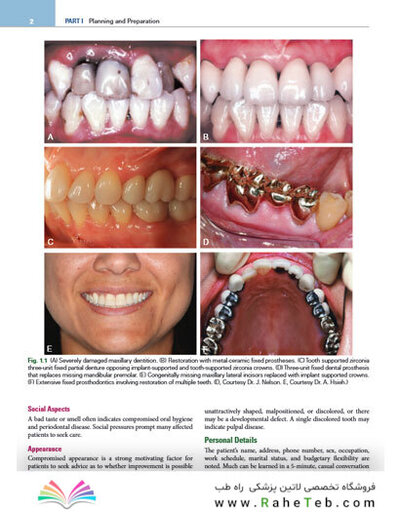

Contemporary Fixed Prosthodontics 6th Edition2023 پروتزهای ثابت معاصر 2023

- تصاویر تمام رنگی باکیفیت